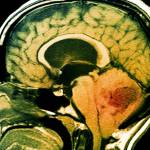

Под термином медуллобластома понимают опухоль головного мозга, расположенная в мозжечке, части мозга, который контролирует баланс, координацию и другие сложные двигательные функции. Медуллобластомы растут чаще всего в центральной части мозжечка и реже в наружных отделах этой части мозга. Медуллобластома составляет от 15 до 20% всех педиатрических мозговых опухолей. Медуллобластомы чаще всего встречаются у детей в возрасте от 3 лет до 8-ми, но возможны у детей и взрослых любого возраста. Около 300 случаев медуллобластомы диагностируется каждый год в нашей стране. Прогноз для детей с медуллобластомой значительно улучшился за последние несколько десятилетий. Исторически врачи классифицировали медуллобластому как стандартную или высокую степень риска на основании результатов биопсии. Однако в последние годы исследования показали, что то, что мы называем медуллобластомой, на самом деле может быть несколькими различными заболеваниями. На сегодня медуллобластома может быть разделена на четыре молекулярных подтипа на основе специфических типов генных мутаций в опухоли. Каждый подтип имеет разную степень выживаемости, варьирующую от 20 до 90%.

Медуллобластома – это злокачественная (агрессивная) опухоль головного мозга, которая начинается в нижней части ствола головного мозга и называется мозжечком. Мозжечок участвует в мышечной координации, равновесии и движении. Медуллобластома имеет тенденцию распространяться через спинномозговую жидкость, которая окружает и защищает ваш головной и спинной мозг — в другие области вокруг головного и спинного мозга. Эта опухоль редко распространяется на другие участки тела.

- Магнитно-резонансную томографию (МРТ): это диагностическая процедура создает детальные изображения структур в головном мозге и позвоночнике. МРТ головного мозга после операции определит, насколько опухоль была удалена хирургическим путем.